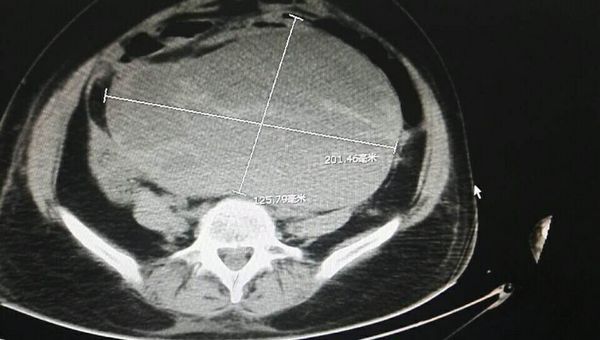

得知该患者情况后,张旭华立即召集团队成员分析病情,制定治疗计划。他们紧急联系肾内科行透析治疗改善肾功能,又调阅她的病史及CT、磁共振等检查,考虑尿毒症为肾后性压迫所致,在局麻下行双侧输尿管双J管置入术。手术效果马上得到体现,第2天复查肾功能指标明显下降,术后第4天,肾功能已完全正常。患者的病情得到初步控制。

但肿瘤压迫是持续的,如何将病灶解除才是治疗的终点。面对省级专家都无法完成的手术,面对经历4次开放手术的腹部,张旭华召集科室人员进行全面讨论,最终决定为患者再次行肿瘤根治术。3月19日,张旭华带领的团队经历8个小时手术,成功将腹腔广泛粘连松解、肿瘤完整切除、侵犯小肠及直肠切除,并行肠吻合及肠造瘘术,术后患者转入普通病房继续治疗。目前,陈女士已恢复饮食,自主活动正常,重获新生。(中国吉安网)